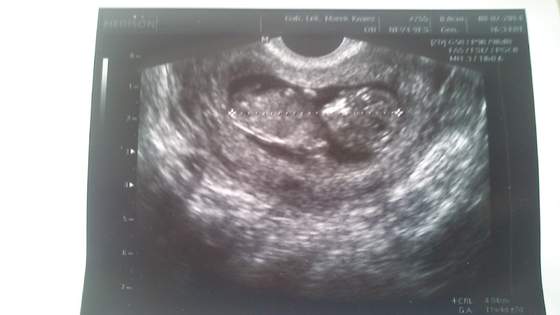

Hej ja po wizycie, bąbel młodszy o 2 dni niz z OM wiec mam sie za tydz pokazac na przeziernosc. Reszta ok, raczki, nozki, zoladek itd itd. Maluch ma 4,84 cm. Ja w pt ide na dokladne usg to moze cosik sie uda podgladnac a na razie taka tylko fotka na szybko. Tak sie wiercil maluch ze nie mozna bylo zrobic ladnego zdjecia